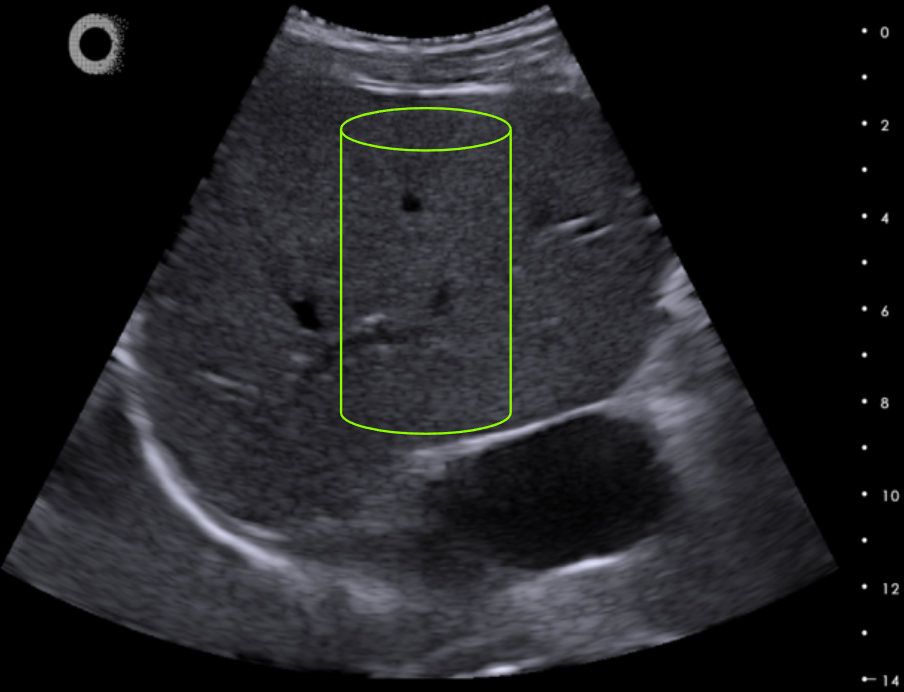

VCTE – Sample Volume = 3 mL

2DTE – Sample Volume = 65 mL

The 2DTE Technology

Hepatoscope 2DTE (two-dimensional transient elastography)is the most advanced ultrasound technology for liver stiffness measurements (LSM), integrating both transient elastography (Catheline, Wu, and Fink 1999) and ultrafast ultrasound (Tanter and Fink 2014) implemented in an ultraportable format.